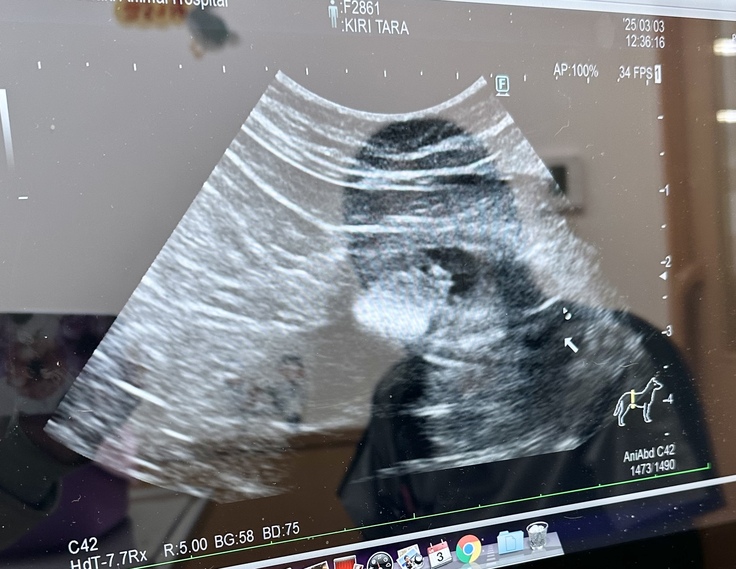

結石の治療開始しました!!

【猫小屋で生活してた猫家族】

鱈(たら)1歳

何度もトイレに行き、血尿が出たので受診しました。

膀胱内に砂状の結石あり、ストルバイトの可能性大ということです。

治療食開始となりましたが食べてくれず。

抗生剤と消炎鎮痛剤で経過観察となりました💧